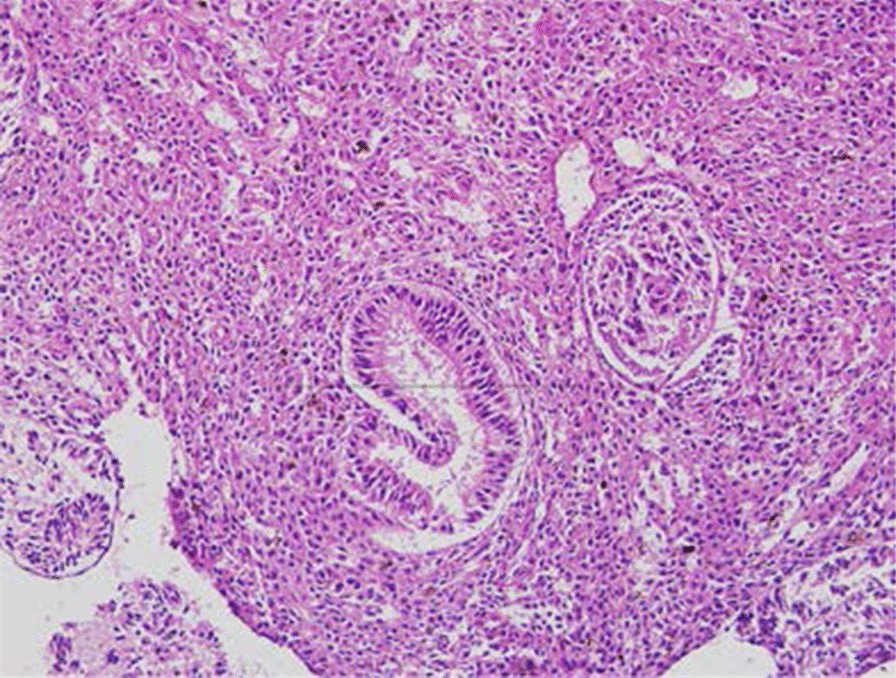

Fig. 2From: Ureteral urothelial carcinoma with squamous cell carcinoma and sarcomatoid carcinoma differentiation: a case reportHigh-grade urothelial carcinoma of the right ureter with differentiation of squamous cell carcinoma and sarcomatoid carcinomaBack to article page